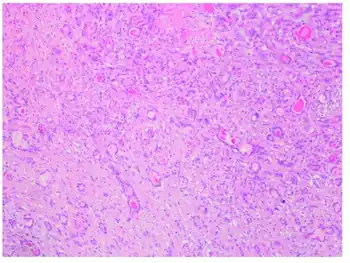

Microscopically, EMECL features bi-layered glandular or ductular structures consisting of inner cuboidal cells and outer multipolar cells.[7]

The histologic appearance of these tumors varied, but all shared the common feature of a biphasic proliferation of epithelial (strong cytokeratin-positive; actin and S-100-negative) and myoepithelial (strong actin and S-100 and focal weak cytokeratin-positive) cells with formation of bilayered ductlike structures. The focal resemblance to other salivary gland-type tumors may cause diagnostic difficulties, particularly in small endobronchial biopsies. Although little is known about their biologic potential due to limited follow-up data, these tumors when in the lung clearly have the capacity to infiltrate and metastasize and therefore should be designated as epithelial-myoepithelial carcinoma. At present, it appears that treatment by complete surgical resection with negative margins alone is appropriate and adequate.[6]